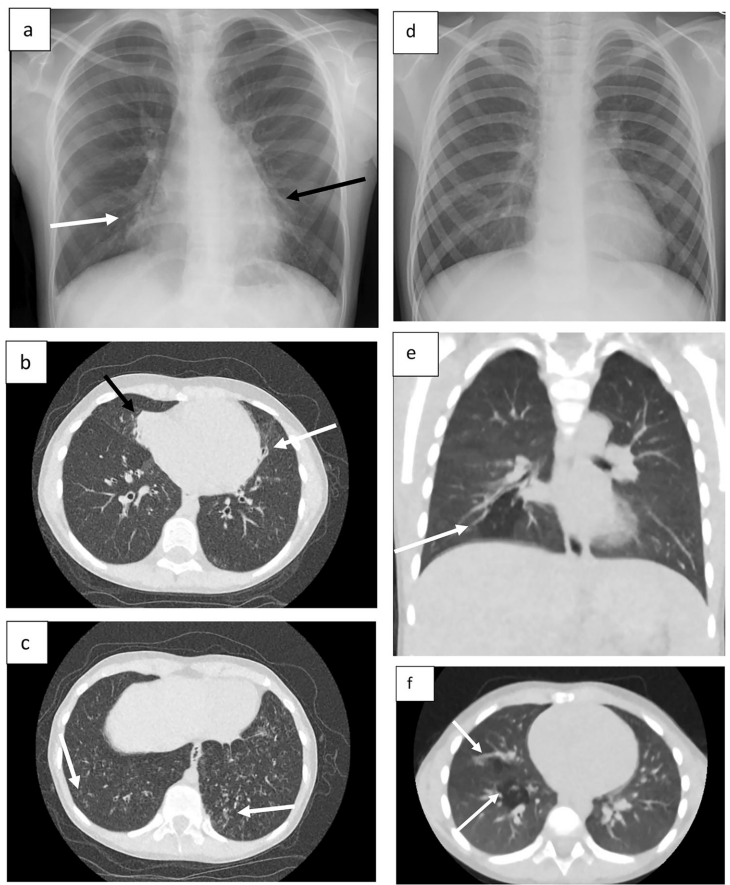

爱尔兰科克大学医学院医学影像与放射治疗学科的研究团队在《European Radiology》发表突破性研究,通过开发辐射剂量媲美CXR的超低剂量CT(ULDCT)方案,采用深度学习迭代重建(DLIR)技术,在保持0.024-0.030mSv超低剂量前提下,使图像噪声控制在9.6±4.3HU,成功实现"鱼与熊掌兼得"。这项多中心前瞻性研究招募25名放射科医师和50名放射技师,对10组配对影像进行盲法评估,发现ULDCT不仅使88%观察者更倾向选择(71/75),其诊断信心评分中位数(30)更显著高于CXR(25)(p<0.001)。视觉分级特征(VGC)分析显示,放射科医师组曲线下面积(AUCVGC)达0.63(95%CI:0.51-0.73),证实ULDCT在支气管壁增厚、粘液栓等CF特征性病变的显示优势。

这项研究从根本上改变了CF监测的剂量权衡范式,证实ULDCT+DLIR技术可突破传统CT的辐射桎梏。其临床意义在于:①为CFTR调节剂时代需要长期影像随访的患儿提供安全方案;②确立0.03mSv级剂量新标准,较Kuo等报道的多中心差异剂量(1.1-7.5mSv)降低两个数量级;③通过图2所示的早期马赛克灌注征检出,使干预时机较肺功能异常提前5-8年。正如讨论指出,随着CF患者预期寿命突破50岁,ULDCT的累积辐射优势将更显著降低继发恶性肿瘤风险。研究团队建议尽快修订国际指南,将ULDCT纳入CF儿童常规监测路径,这将是自2012年CFTR调节剂问世以来,CF管理标准的又一次重大革新。